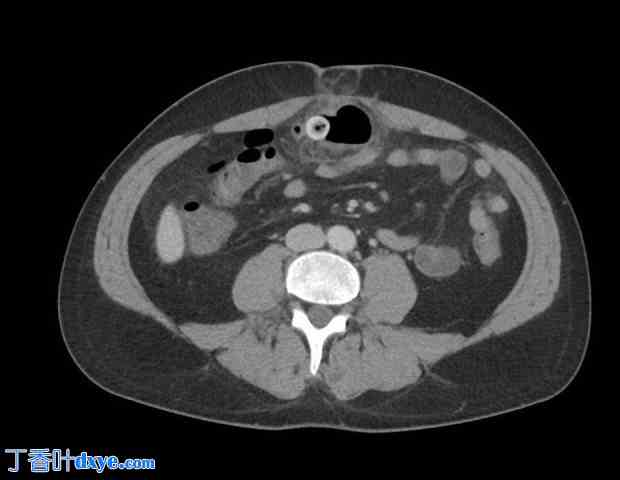

图 2. CT 扫描显示疝出内容物和炎症进展。

略微颅骨水平的轴向 CT 扫描显示疝出的腹膜前内容物进展,周围有脂肪条带和空气包裹体。腹壁缺损和嵌顿节段的位置清晰可见。

这排除了肠穿孔的间接或直接证据的可能性,从而确认了脐疝嵌顿伴缺血性肠内容物的诊断。疝内容物未被描述为Meckel憩室。